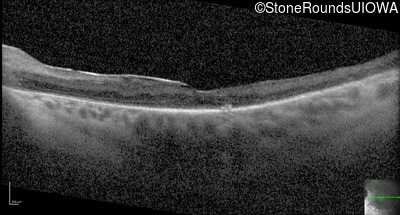

Optical Coherence Tomography - Left - 20/30 +2

Exemplar / OCT Stack

OCT Stack